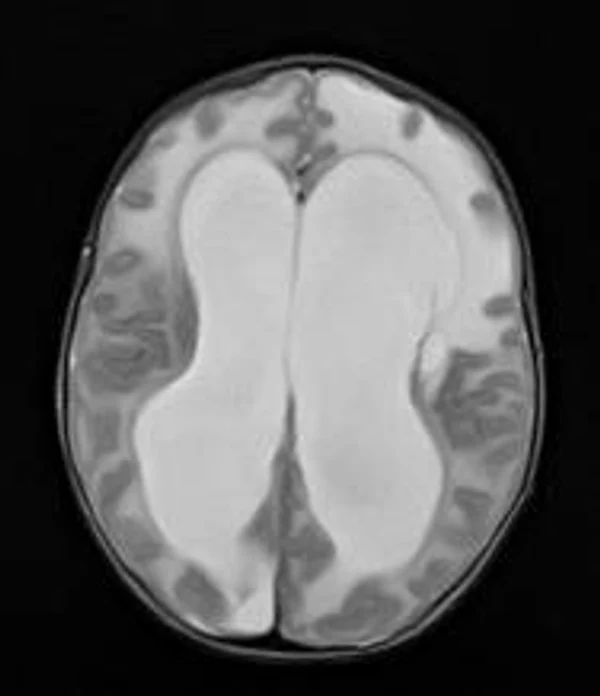

Гидроцефалия

Основной причиной гидроцефалии является окклюзия ликворных путей, встречающаяся у новорожденных детей в 60-70% случаев, к 3 годам частота окклюзионной гидроцефалии достигает 90%. Поэтому основной задачей лечения гидроцефалии являются устранение окклюзии ликворных путей, восстановление циркуляции ликвора и нормализация внутричерепного давления. В настоящее время эти задачи успешно позволяют решить эндоскопические методы хирургического лечения гидроцефалии. Эндоскопические операции проводятся нами во всех возрастных группах, включая недоношенных новорожденных детей, при разных локализациях и количествах окклюзий. При этом если эндоскопическая перфорация дна III желудочка (син.: эндоскопическая III-вентрикулостомия) малоэффективна у детей до 2-3-х летнего возраста, то новые методы эндоскопических операций, направленные на реканализацию естественных путей оттока ликвора с имплантацией стента (например эндоскопическая акведуктопластика, стентирование водопровода мозга) позволяют избежать имплантации шунтирующих систем у большинства пациентов с окклюзионными формами гидроцефалии. С целью снижение объема секреции ликвора и увеличения эффективности эндоскопических опеарций в некоторых случаях в комплексе с другими эндоскопическими операциями проводится эндоскопическая плексусэктомия. Операция заключается в коагуляции сосудистых сплетений боковых желудочков с последующим удалением их гломусных частей. Эндоскопические операции также проводятся при дисфункции ранее установленных шунтирующих систем у пациентов с окклюзионной гидроцефалией, что часто избавляет пациента от «шунт зависимости» и создает условия для удаления шунта. Имплантация ветрикулоперитонеальных, вентрикулоатриальных и др. шунтирующих систем нами применяется при сообщающейся форме гидроцефалии. У пациентов с окклюзионными формами гидроцефалии шунтирующие операции проводятся только при неэффективности ранее проведенных эндоскопических операций.